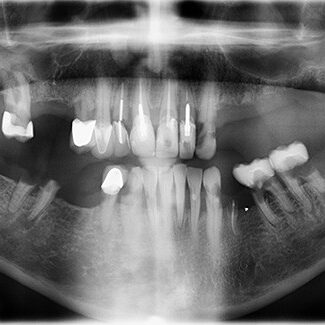

Before and After

SEE OUR RESULTS